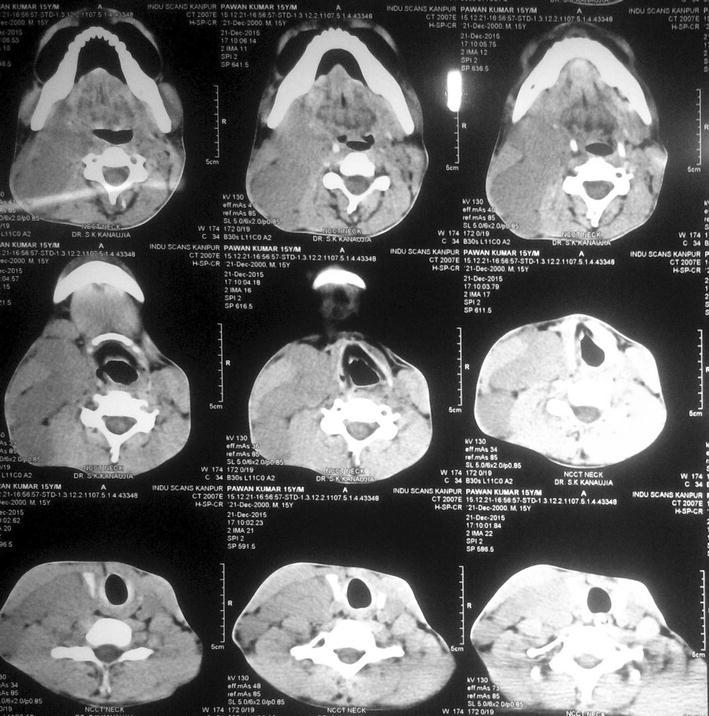

A fifteen year old boy was presented to our hospital with chief complaints of painless progressive swelling in the right side of neck in last 6 months. Patient was having no history of fever, pain in throat, difficulty in deglutition, difficulty in respiration, chronic cough, loss of appetite or loss of weight. On examination there was non-tender, non-fluctuant soft to firm swelling involving anterior and posterior triangle of neck about 10 × 6.5 cm in dimension on right side. It was mobile and not adherent to underlying skin (Figs. 1, 2). There was also swelling involving bilateral supraclavicular region. There was no any swelling in axillary or inguinal region. On nasal endoscopy no abnormality was detected. Routine haematological examination showed Haemoglobin 12.2 g%, Total leukocyte count 6.3 × 109/litre, Erythrocyte sedimentation rate 15 mm 1st hour while differential leukocyte count was with in normal limits. Mantoux test was negative. High resolution Ultrasonography suggested multiple discrete, homogenous lymph node in right carotid space. There was no cystic necrotization, calcification or loss of fibrofatty plane are seen (Fig. 3). Contrast enhanced computed tomogram neck with thorax suggested a large lobulated soft tissue lesion about 10 × 6.5 × 5.5 cm in dimension (Fig. 4). No intratumoral necrosis was seen. Patchy heterogeneous enhancement was seen in post contrast images. Mass was mildly compressing trachea and right thyroid gland to the left (Figs. 5, 6). Bilateral supraclavicular lymph node was seen along with non-necrotic lymph node in superior mediastinum. Fine needle aspiration cytology from cervical lymph node was highly suggestive of Rosai–Dorfman disease, however biopsy was advised for confirmation. Biopsy was done under local anaesthesia from the posterior triangle of neck just behind the mid part of sternocleidomastoid muscle. Histopathology showed diffuse effacement of lymph node architecture and dilated sinuses distended with benign histiocytes (Figs. 7, 8); the diagnosis was given as sinus histiocytosis with massive lymphadenopathy (Rosai–Dorfman disease). This patient was put on oral prednisolone 10 mg three times a day in tapering doses for 21 days initially and then on low dose of steroids for next 4 months. The patient showed marked clinical improvement.

Fig. 5.

CT scan axial view 1

Fig. 6.

CT scan axial view 2